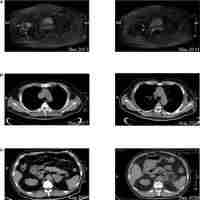

| Description | Background and Objectives: Third-generation epidermal growth factor receptor (EGFR)-tyrosine kinase inhibitor (TKI) is one of the standard-of-care therapies in patients with EGFR-mutant lung adenocarcinoma; however, acquired resistance inevitably developed. Despite the proposition of histological transformation being one of the resistance mechanisms, its incidence and influence on outcome remain unclear. Materials and Methods: This was a retrospective study conducted at Taichung Veterans General Hospital on patients with advanced EGFR-mutant lung adenocarcinoma receiving the third-generation EGFR-TKI. Only patients receiving rebiopsy were included in the analysis. Results: A total of 55 patients were studied. Eight patients (14.5%) showed histological transformation, including three small cell carcinoma, three squamous cell carcinoma, one large cell neuroendocrine carcinoma, and one with a mixture of adenocarcinoma and squamous cell carcinoma components. The median treatment duration of the third-generation EGFR-TKI before rebiopsy was numerically longer in patients with histological transformation than those without (16.0 vs. 10.9 months). Both the overall survival time from the start of third-generation EGFR-TKI initiation (30.8 vs. 41.2 months) and from rebiopsy (6.6 vs. 12.9 months) to mortality were numerically shorter amongst the transformed population. All patients in the transformed group did not respond to the next line of systemic treatment. One patient with histological transformation receiving local treatment for the metastatic site had a longer overall survival. Conclusions: Repeating biopsy to identify histological transformation should be considered in patients with progression to the third-generation EGFR-TKI. Histological transformations could contribute to the acquired resistance with the implication of a worse prognosis. Further studies are needed to determine the optimal therapy for these patients. |